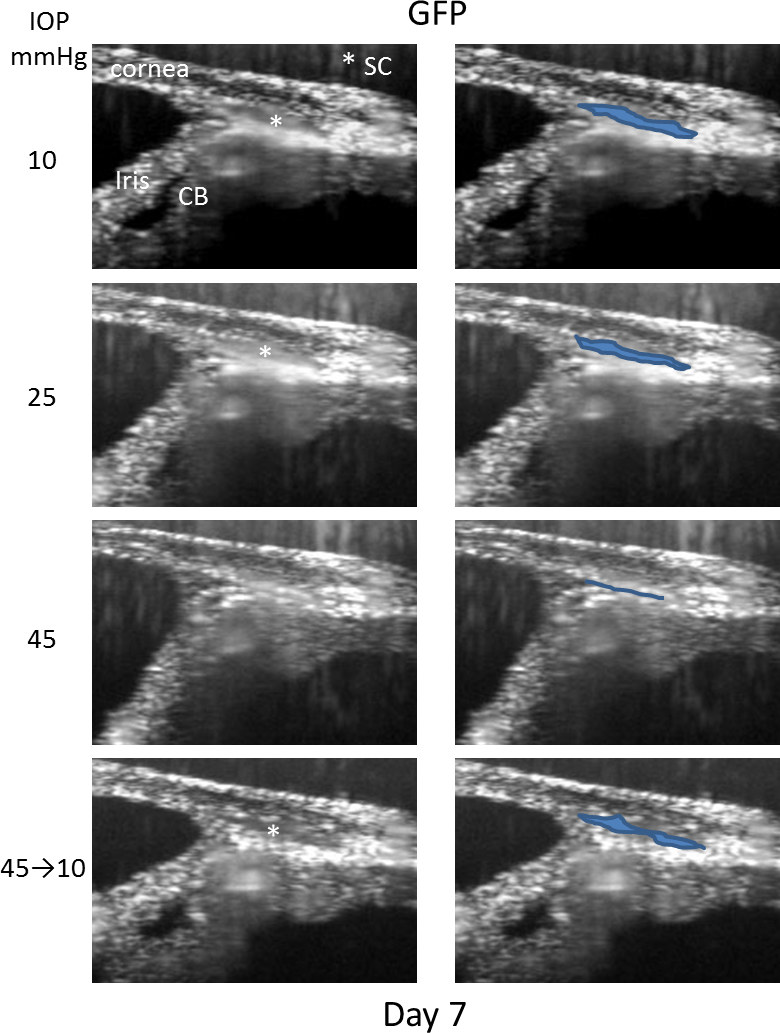

Figure 7. Example of SC lumen segmentation derived from OCT images of mouse eyes subjected to changes in IOP. In the left column are

the average intensity images of the same region of a mouse anterior eye held sequentially at 10, 25, 45, and 10 mmHg. In the

right column, the images are reproduced, and the SC lumen is outlined and highlighted. Asterisk shows the location of the

SC lumen. CB=ciliary body. Images shown were obtained from one mouse out of a total of three control mice that were segmented.